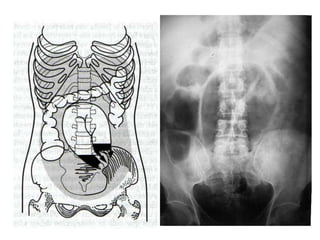

• Estrangulación

• Pocos niveles hidroaéreos

• En radiografías seriadas no cambia de localización

• Imagen en grano de café: Obstrucción incompleta en

asa cerrada

• Neumoperitoneo perforación

• Líquido libre intraperitoneal

– Se acumula en pelvis (signo de las orejas de

perro) y asciende por gotieras paracólicas

(signo del flanco)

– Imagen homogénea de densidad agua